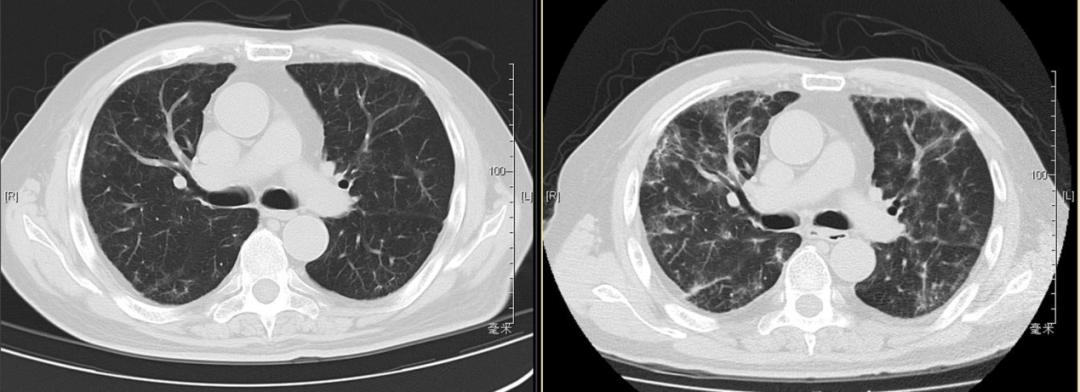

本院胸部CT(2019-08-30)示: 双肺弥漫性间质性改变,有网格状改变、毛玻璃影、局部有支气管牵拉形成支气管扩张的表现。

追溯患者2018年体检胸部CT(2018-1-22) :两肺下叶轻度间质增生,无显著双肺弥漫性间质改变。而且近一个月出现气促症状、低氧血症,说明间质性病变有活动性。